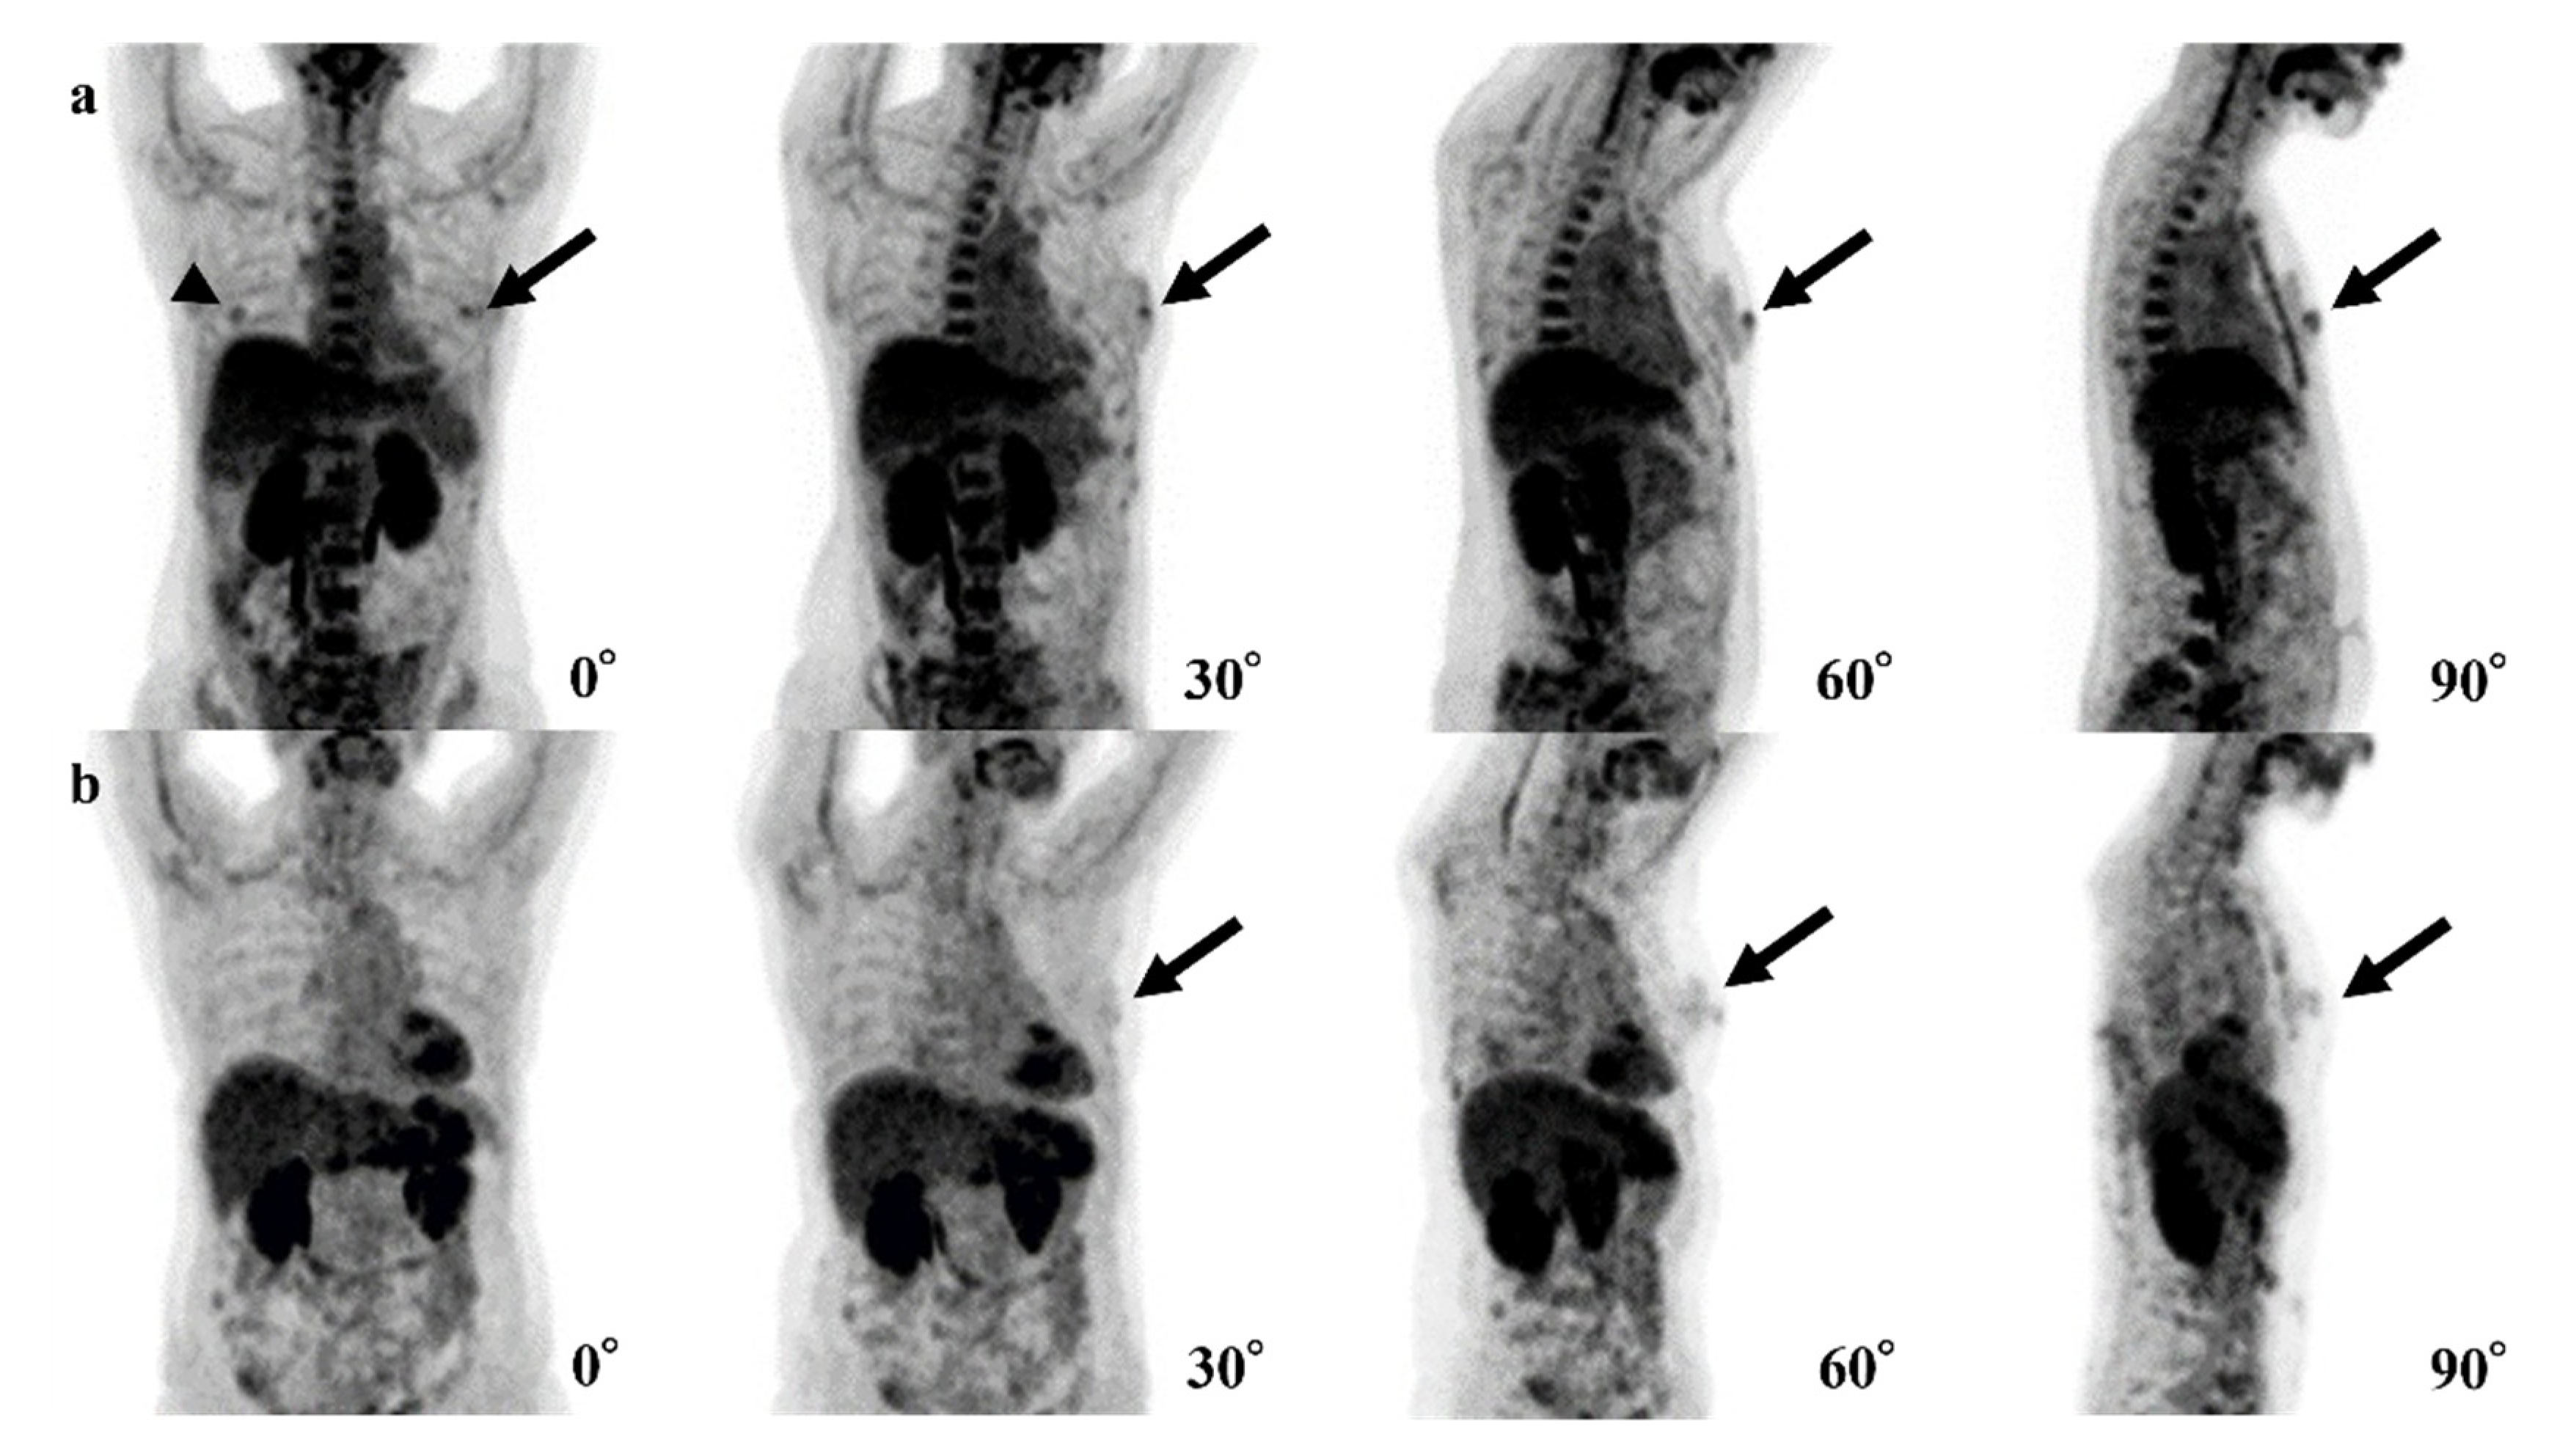

Figure 3.

Examples of false-positive cases of the 4-degree model are shown. (a) The fluorodeoxyglucose (FDG) uptake of both nipples (left; black arrows, right; arrowhead) could be confirmed in the 0° positron emission tomography (PET) maximum-intensity projection (MIP) image, but the uptake of the right nipple disappears in 30°, 60°, and 90° PET MIP images. (b) Physiological FDG uptake of a mammary gland or a nipple (black arrows) could be recognized as a breast lesion.

In our 4-degree model, there were 10 false-positive (Figure 3) and three false-negative cases (Figure 4). Among these 10 false-positive cases, four cases had physiological FDG uptake at both (2 cases) or left (2 cases) mammary glands resembling masses; four cases had both nipples with physiological FDG uptake, but 1 of them disappeared in 30°, 60°, or 90° MIP.

In 4 of 10 false-positive cases of the 4-degree model, it is possible that our 4-degree model misrecognized normal FDG uptake of one nipple as BC. Because FDG uptake of the heart is typically higher than that of nipples, it is considered that the model could not recognize one nipple overlapping with the heart and presume the other nipple was the breast abnormality (Figure 4a). In the other four cases, the model may have misrecognized normal but mass-like FDG uptake of a mammary gland or a nipple as a breast lesion (Figure 4b).